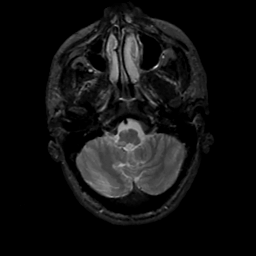

MR Study #2, February 17, 1991 -- Slice #8

[Home][Help][Clinical][Tour 1][Tour 2] Slice 8